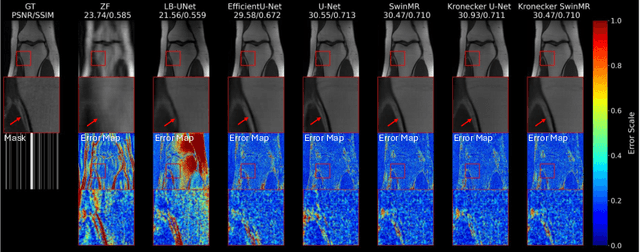

Abstract:Magnetic Resonance Imaging (MRI) is crucial for clinical diagnostics but is hindered by prolonged scan times. Current deep learning models enhance MRI reconstruction but are often memory-intensive and unsuitable for resource-limited systems. This paper introduces a lightweight MRI reconstruction model leveraging Kronecker-Parameterized Hypercomplex Neural Networks to achieve high performance with reduced parameters. By integrating Kronecker-based modules, including Kronecker MLP, Kronecker Window Attention, and Kronecker Convolution, the proposed model efficiently extracts spatial features while preserving representational power. We introduce Kronecker U-Net and Kronecker SwinMR, which maintain high reconstruction quality with approximately 50% fewer parameters compared to existing models. Experimental evaluation on the FastMRI dataset demonstrates competitive PSNR, SSIM, and LPIPS metrics, even at high acceleration factors (8x and 16x), with no significant performance drop. Additionally, Kronecker variants exhibit superior generalization and reduced overfitting on limited datasets, facilitating efficient MRI reconstruction on hardware-constrained systems. This approach sets a new benchmark for parameter-efficient medical imaging models.